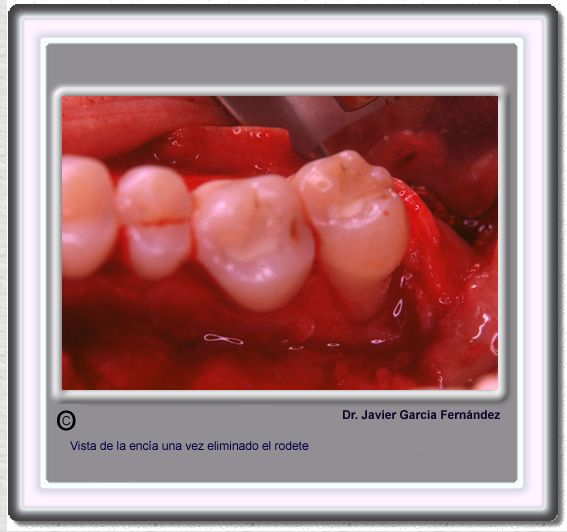

image 215